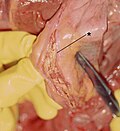

Gross

- Entry intimal tear +/- exit intimal tear.

- Blood between layers of the vessel wall.